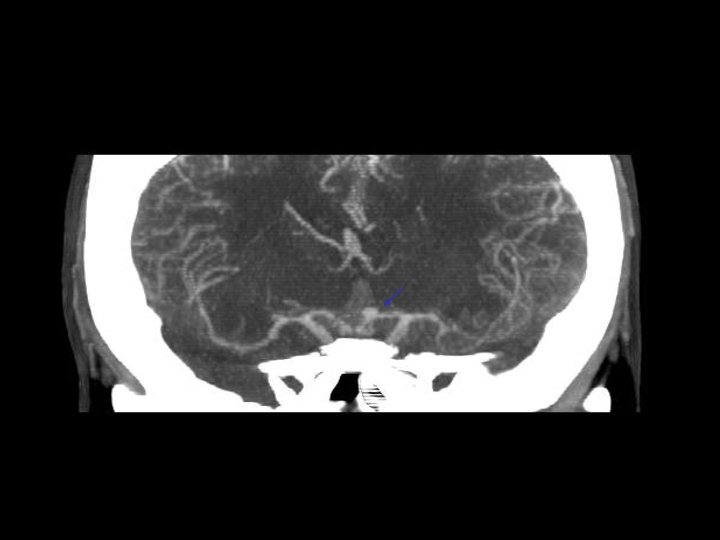

Subarachnoid hemorrage n Dapat timbul dari jejas langsung ke pembuluh darah, contused cortex atau perdarahan intraventricular n Lihat pada sisterna interpeduncular dan fisura Sylvii n Biasanya focal (namun dapat difus kalau berasal dari aneurisma) n Dapat menyebabkan communicating hydrocephalus

POST TRAUMATIC SEQUELAE n Carotid-cavernous fistula(CCF) n Dissection/pseudoaneurysm n Infarction n Atrophy/encephalomalacia n Infection n Leptomeningeal cyst